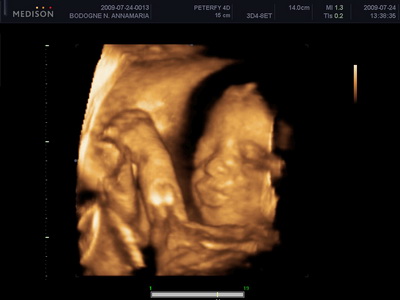

Mi megvagyunk, növögetünk ezerrel. Pénteken voltunk 4d-n, minden rendben van. Lilike most már biztos hogy Lilike, nem szégyenlős a drágám, rendesen bepucsított és szép kis hurija is van. 1000g-nak mérték és azt mondta a doktornő, hogy készüljünk, hogy szép nagy baba lesz. Nem a súlya lesz óriási, hanem szép hosszú lesz, lehet hogy 58-60 cm :lol: Mondjuk erre számítottunk mert mi se vagyunk alacsonyak :lol: Egyébként tiszta apja a kis drága. Nagy csókos szája van és kis kerek arcocskája. Teljesen beleszerettem :lol: Még puszit is küldött nekünk a kis husi szájával. Teszek fel pár képet nektek.

Kis csókos szájú

Vitathatatlan nunis

Nyitott szemmel